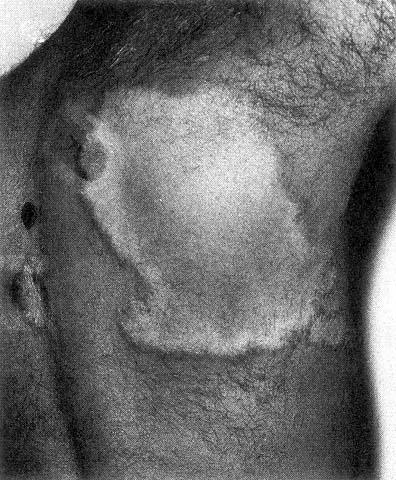

TUBERCULOID LEPROSY

Tuberculoid leprosy (TT) - few skin lesions.

Skin lesions - hypopigmented macules and plaques (common), papules and nodules (rare)

Reddish patches or hypopigmented areas of skin with reduced sensation.